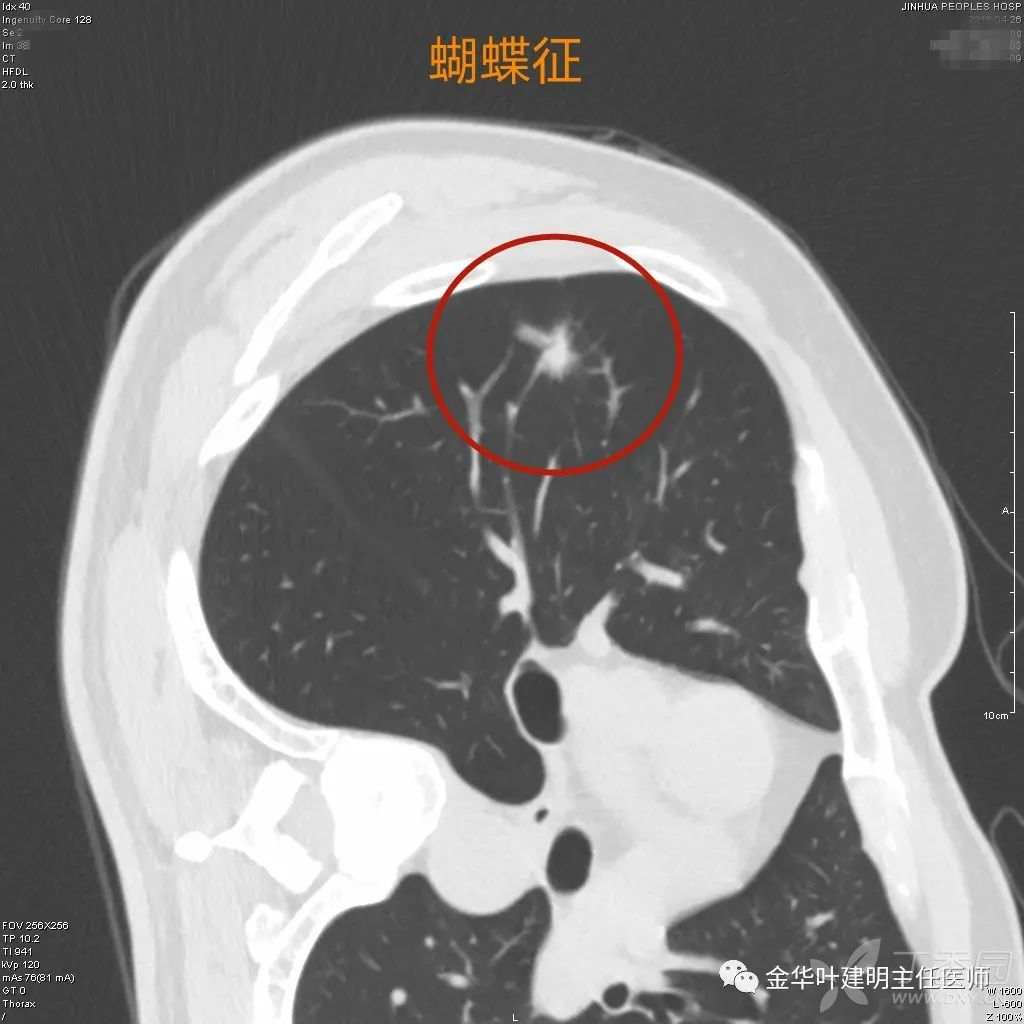

蝴蝶征

蝴蝶征:混合磨玻璃结节容易有这种表现,中间有收缩纠集,两边像蝴蝶的翅膀伸展开,其实是病灶有收缩力的外在表现,说明质地硬,中间密度高的部分更是密实,边缘含磨玻璃成份的相对不太密些,所以有这样的影像表现。